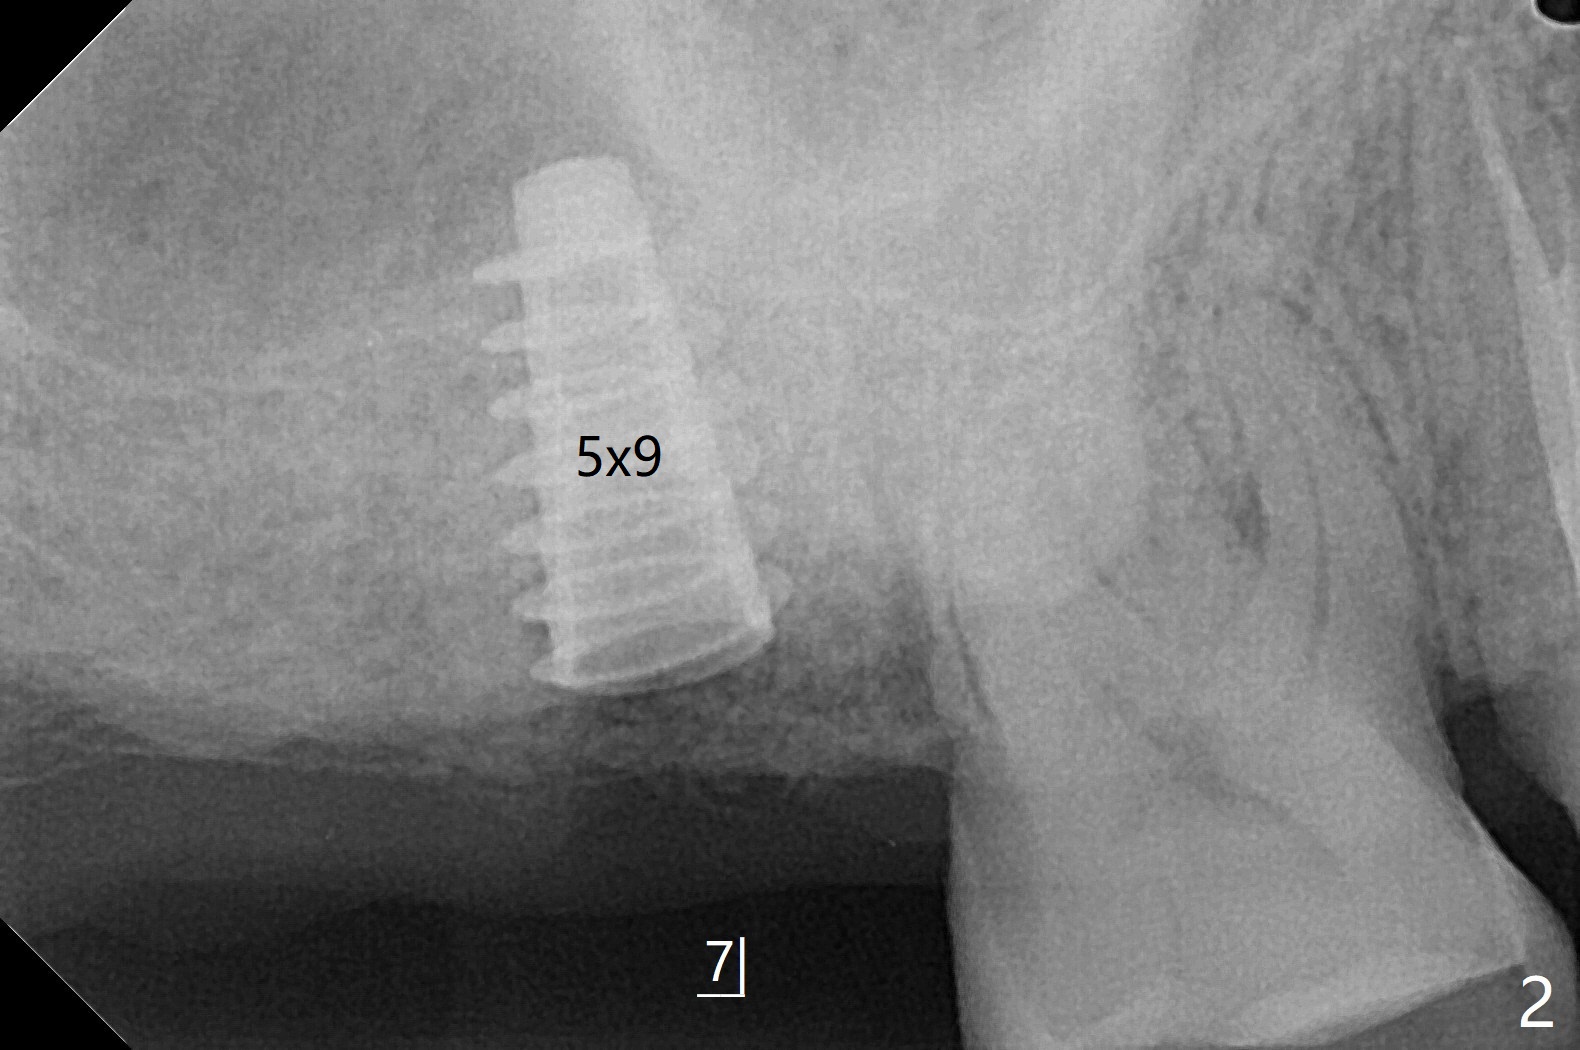

2号牙位点保存后6个月,而15号牙拔除没有植骨1-2年前(图一)。2号牙位骨质高度足够,准备不做上颌窦提升(图二),而15号牙位需要提升(图三,六)。种植术后5个月两个植体愈合均正常(图十一,十二)。